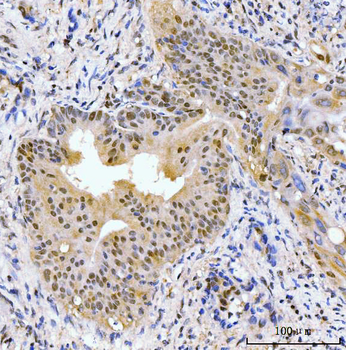

AKAP8 Antibody

| Description | AKAP8 Antibody |

| Tested applications | IHC |

| Reactivity | Human |

| Dilution range | IHC: 1/20-1/100 |